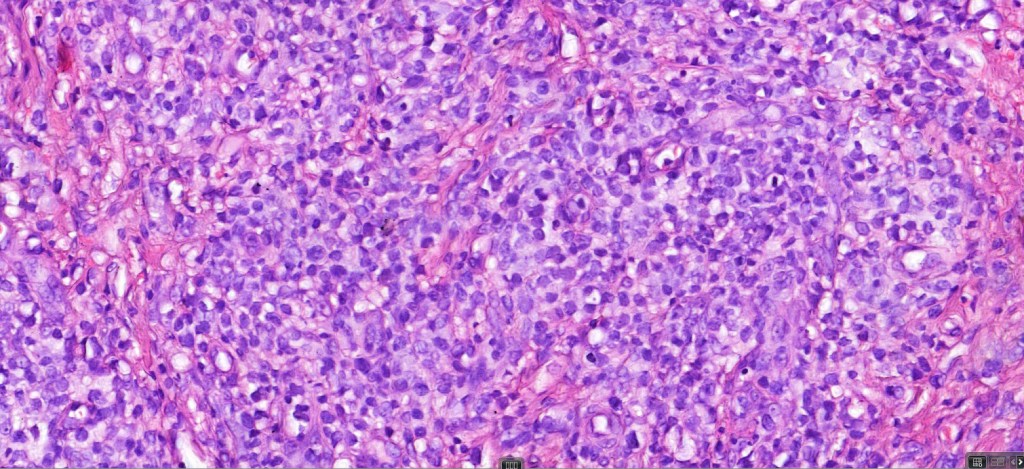

Histological features

The histological hallmark of mycosis fungoides is the presence of large atypical lymphocytes with a convoluted/cerebriform nuclear border (Sézary cells). These may be found at the epidermal-dermal jnuction and as collections within the epidermis (Pautrier microabscess). These are most easily found in plaque stage disease. The epidermal component can be subtle in patch stage disease and is often lost in tumor stage dsease. The classification into patch, plaque & tumor stage disease is less helpful histologically as the features merge from one to the other. It is all a matter of degree.

Plaque Stage Disease

•Compact hyperkeratosis & patchy parakeratosis

•Acanthosis

•Psoriasiform hyperplasia common

•Epidermotropism is often marked with conspicuous Pautrier microabscesses

•Superficial band-like dermal infiltrate of atypical lymphocytes, eosinophils, plasma cells & histiocytes

Tumor Stage Disease

•Epidermotropism is often minimal or absent

•Dense, broad diffuse or nodular, dermal infiltrate often extending into the subcutaneous fat

•Abundant Sézary cells. Frequently accompanied by very pleomorphic forms

•Mitoses often abundant, frequently abnormal